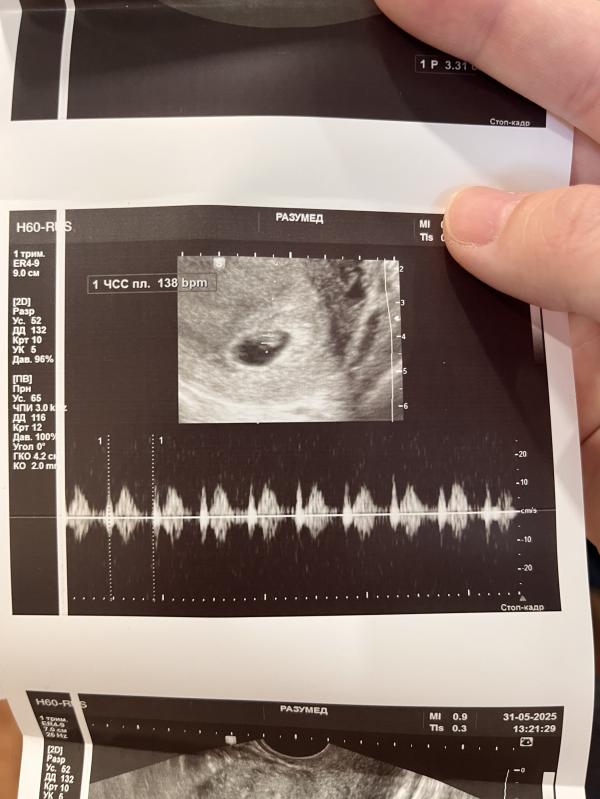

Сходила на повторное УЗИ, сердечко бьется , все хорошо , все показатели в норме 🥹🥲🙏🏽

Нам уже 7 неделек 🥰🥹